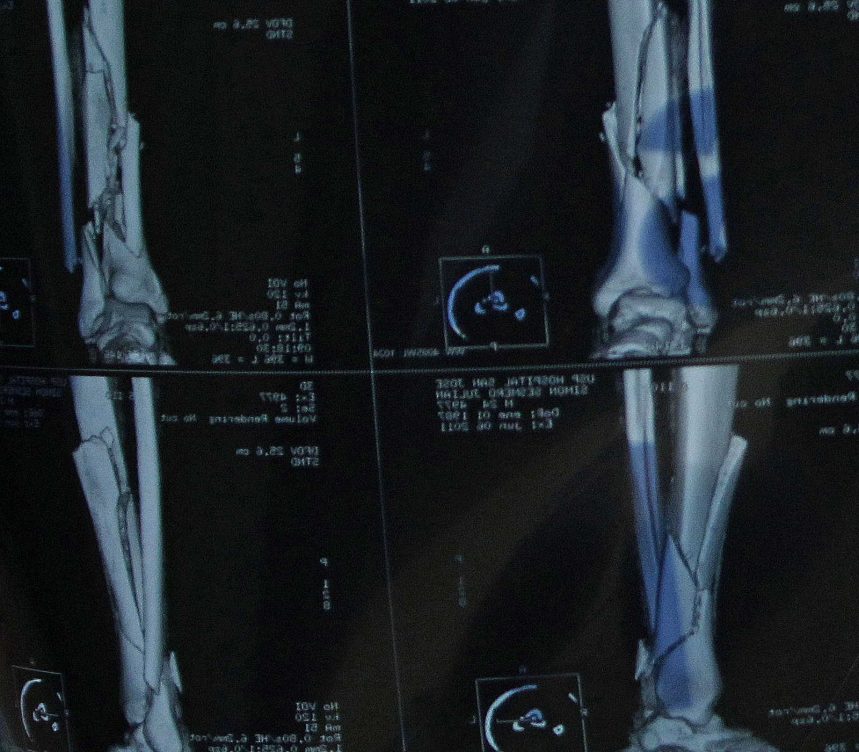

Con la radiografía se comprobará qué tipo de fractura sufre el peroné: si es limpia (sin fragmentaciones) o si existe algún desplazamiento; además, se verán otras lesiones óseas en la tibia y en el astrágalo o daños en los ligamentos articulares.

Si la fractura es limpia solo hay que inmovilizar el peroné y vigilar de cerca su evolución, «de forma exhaustiva», no vaya a ser que, una vez se haya reducido la inflamación, se produzca, ahora sí, cierto desplazamiento de la zona fracturada al apoyar la pierna o el pie; lo que requeriría una intervención quirúrgica.

Si la fractura no es limpia, directamente a quirófano.

“La traumatóloga recolocará en su sitio las distintas partes del peroné con placas y tornillos. Tiene que conseguir una reducción exacta, ya que el juego de la articulación superior del tobillo, junto a la tibia y el astrágalo, debe ser natural, sin fricciones innecesarias. De lo contrario, estaremos generando dolor y artrosis crónica”, dice cargada de experiencia.